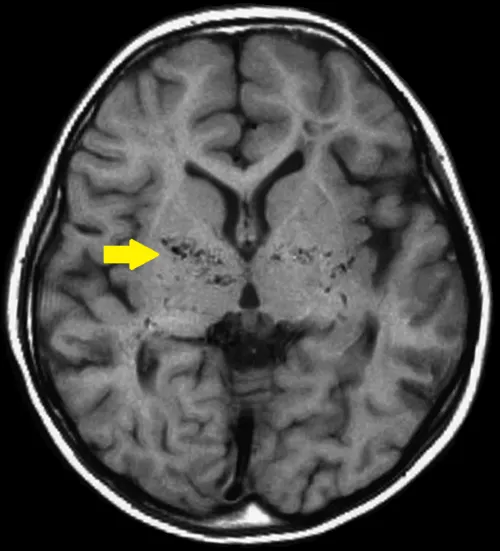

두개 내 양측 내경동맥 말단부위나 주요 가지 동맥의 점차적인 폐쇄로 특징적인 소견을 통해 진단합니다. 뇌 혈관 조영술에서 연기 같은 미세한 혈관들이 관찰되면 모야모야병으로 진단됩니다. 뇌혈역학적 검사(SPECT)를 통해 혈역학적 스트레스 정도를 평가하고 치료 방침을 결정합니다.